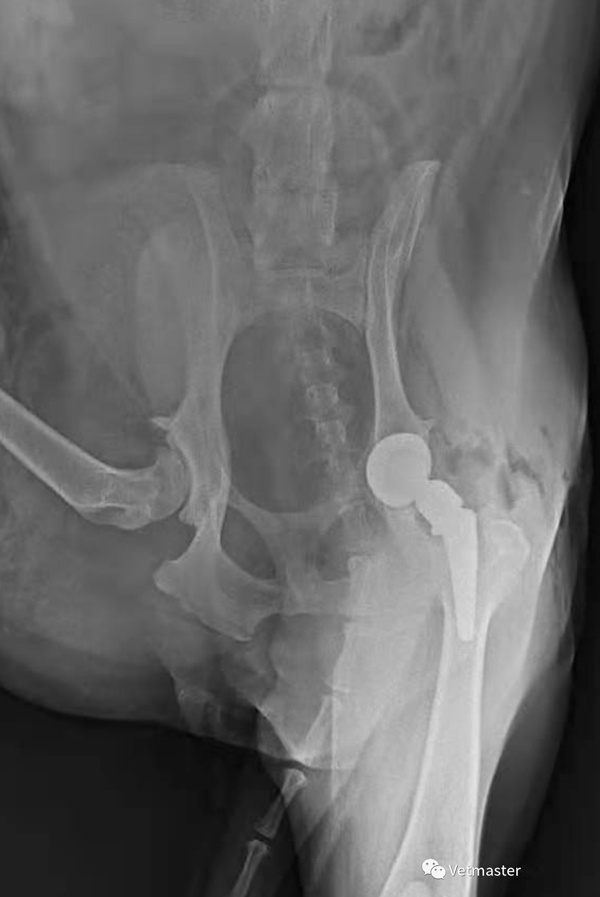

As the owner of a dog, facing the major medical decision of hip replacement surgery, it is necessary to comprehensively evaluate from multiple dimensions such as hospital qualifications, doctor experience, implant brand, and postoperative care.

Equipment conditions: Priority should be given to hospitals equipped with digital X-ray machines (DR), CT, and laminar flow operating rooms to ensure accurate preoperative diagnosis and sterile environment during surgery.

Clinical experience: Whether the lead surgeon has sufficient experience in small animal hip replacement surgery, they can request past surgical cases or search for relevant cases through online platforms.

4. The key action of postoperative care is the golden recovery period (8-12 weeks after surgery). Activities should be restricted mainly by cage care, and jumping/climbing stairs should be avoided; Physical therapy: exercise under the guidance of a veterinarian; Nutritional support: Is it necessary to supplement joint nutrients (such as glucosamine, Omega-3) to control weight and reduce joint load. Long term monitoring and regular X-ray imaging to evaluate the stability of prostheses; If limping recurs, seek medical attention immediately and check for infection or loosening of the prosthesis.